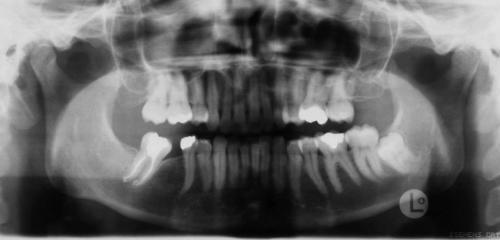

Röntgenbefunde

Links Röntgenbefund vor der Behandlung, rechts Zustand während der Behandlung. Die Lücke im Unterkiefer rechts (linke Seite auf dem Röntgenbild) wurde durch Vorbewegen und Aufrichten des endständigen (wurzelgefüllten) Backenzahnes geschlossen. Prothetische Maßnahmen wurden dadurch überflüssig, außerdem verbesserten sich die Verhältnisse für den Zahnhalteapparat dieses Zahnes deutlich. Der Weisheitszahn im Unterkiefer links wurde vor der chirurgischen Vorverlagerung des Unterkiefers entfernt, um eine ungünstige Trennung der Knochenfragmente zu vermeiden.